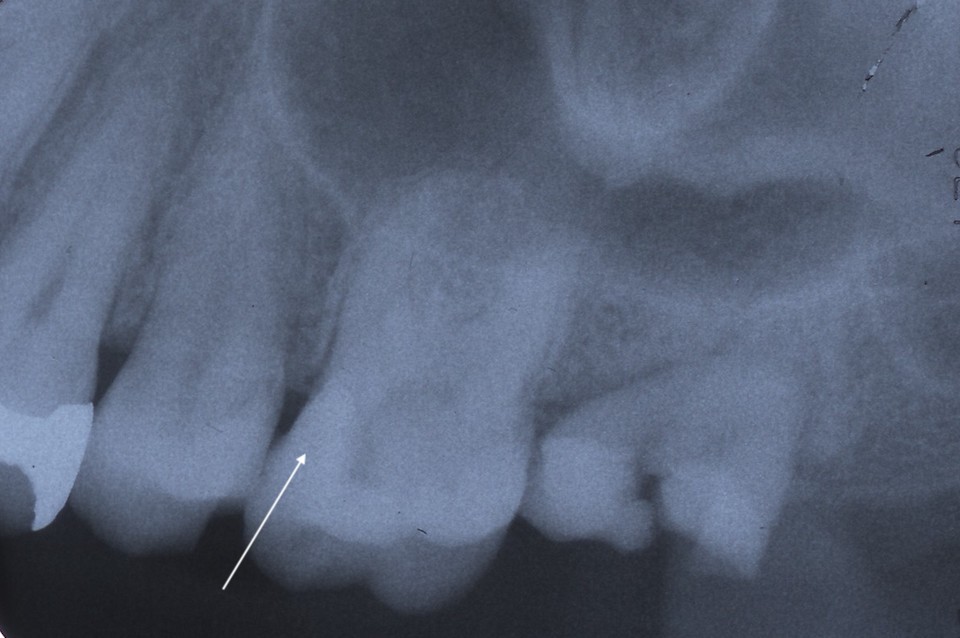

下顎7番の頬側歯茎部カリエスの原因 2025.06.04